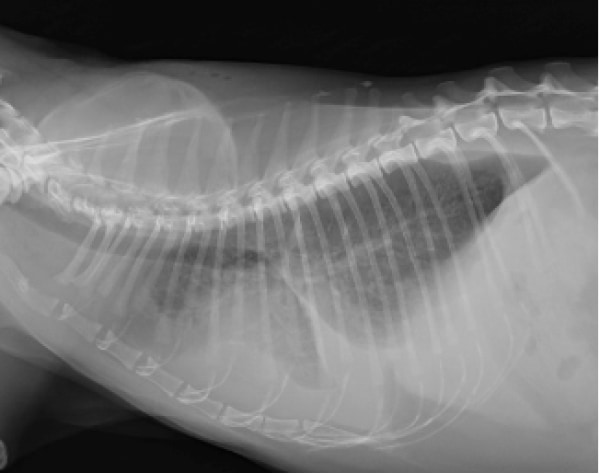

診断は身体検査、超音波検査、レントゲン検査、血圧測定、心電図、血液検査などにより総合的に行います。治療は心臓の負荷を軽減する薬による治療が一般的です。一部施設では手術による治療も行われています。(手術をご希望の方は施設をご紹介いたします)